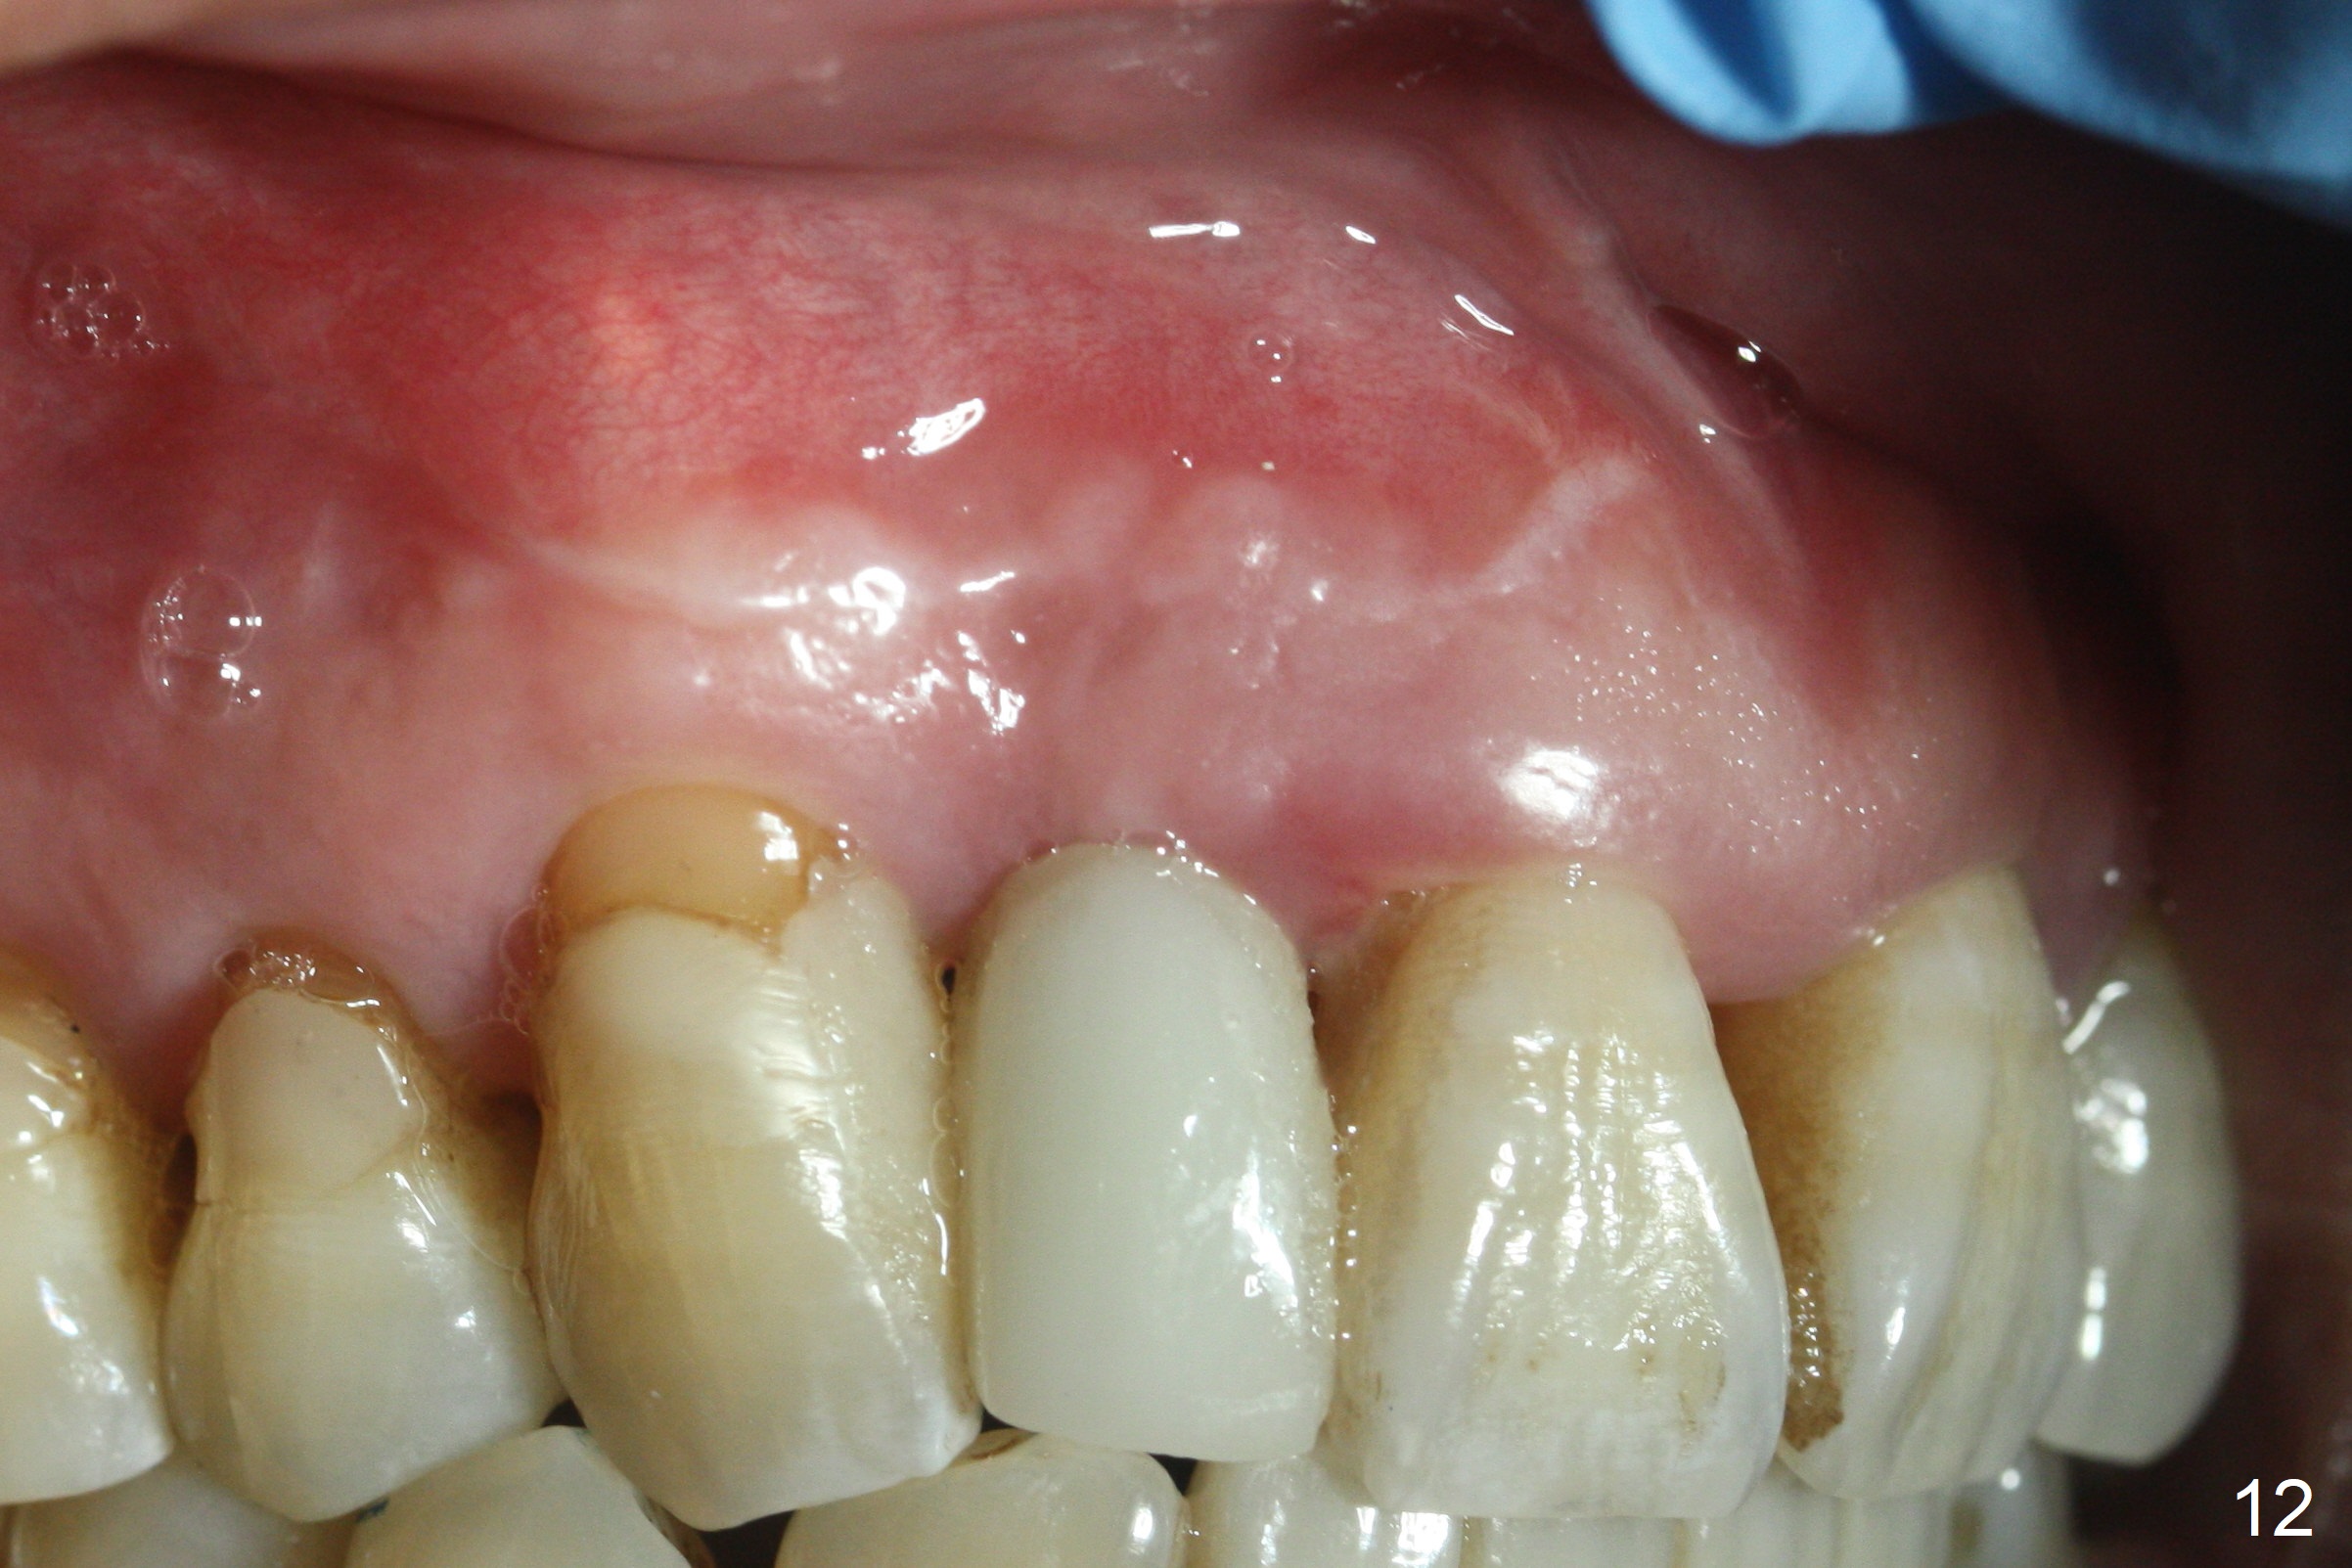

Preop exam shows the apparent wide ridge at #7 (Fig.1). What is ignored preop is the concavity in the apical buccal region (Fig.2 *). When a 3x16(4) mm 1-piece implant is being placed (Fig.3 *, flapless), the apical buccal plate vibration is felt. The biggest mistake is that initial osteotomy is ~ 6 mm shy of the implant length, partially because of 6 mm gingival height. Since the tooth #6 is symptomatic after RCT with paste overfill (Fig.4 >), apicoectomy is contemplated at #6 with exploration of the buccal plate at #7 (Fig.5). Since the implant appears to be long enough, implant apical resection is performed (Fig.6). Since there is coronal thread exposure due to previous periodontitis (Fig.7 <), bone graft is placed in these 3 defective areas after decortication.

Extending the initial osteotomy to the full length of the implant is critical. If perforation is detected early, the trajectory can be changed. Incision should be made if there is no CBCT study. The incision heals 1 and 4 weeks postop (Fig.8,9). The patient returns for final restoration 6 months postop. Apical defects appear to have healed at #6 and 7 (Fig.10,11). Fig.12 is taken 11 months postop and 5 months post cementation. The patient has an accident 9 months post cementation. In fact the implant is alright, while the tooth #6 fractures and #8 subluxates.